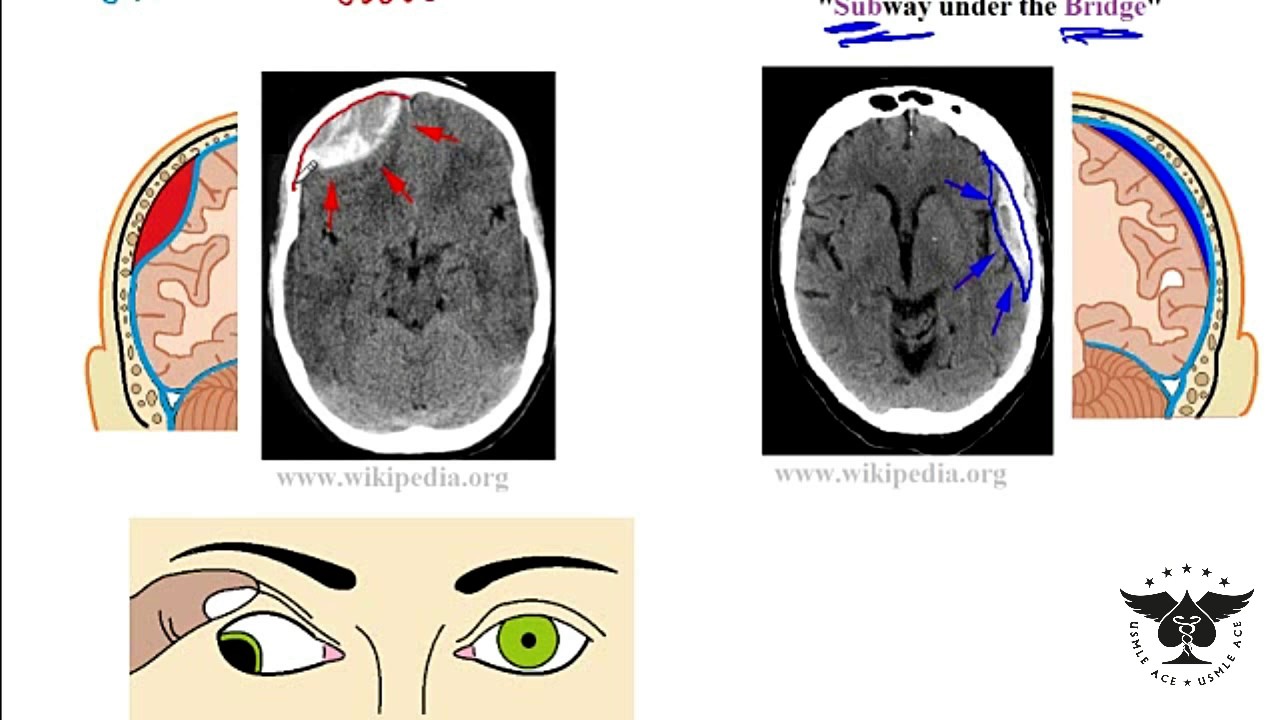

Epidural Hematoma Vs Subdural Hematoma Understanding The Differences It’s important to know the difference between a stroke and a subdural hematoma. both are serious brain issues that can cause big problems. strokes and subdural hematomas are sudden events that affect the brain a lot. what is a stroke? a stroke happens when a blood vessel in the brain gets blocked or bursts. Stroke and subdural hematoma are interconnected and can have devastating effects. understand the link between these two serious medical conditions and how they impact brain health. It’s hard to tell the difference between a subdural hematoma and a stroke. both are serious, but they come from different causes and need different treatments. a subdural hematoma is when blood gathers between the brain and its outer layer. a stroke, or cerebrovascular accident, happens when blood doesn’t reach part of the brain. The only way to differentiate between stroke and chronic subdural hematoma, regardless of symptoms, is with a ct scan of the brain. don’t assume that someone’s symptoms must mean chronic subdural hematoma just because he hit his head recently, either; it can still be a stroke, unrelated to the head trauma.

Download Subdural Hematoma Vs Epidural Hematoma Intracranial It’s hard to tell the difference between a subdural hematoma and a stroke. both are serious, but they come from different causes and need different treatments. a subdural hematoma is when blood gathers between the brain and its outer layer. a stroke, or cerebrovascular accident, happens when blood doesn’t reach part of the brain. The only way to differentiate between stroke and chronic subdural hematoma, regardless of symptoms, is with a ct scan of the brain. don’t assume that someone’s symptoms must mean chronic subdural hematoma just because he hit his head recently, either; it can still be a stroke, unrelated to the head trauma. Subdural hematoma: bleeding between the brain and the dura mater, the outermost membrane covering the brain. now, you might be wondering, “are all brain bleeds considered strokes?” the answer is no. while hemorrhagic strokes are a type of brain bleed, not all brain bleeds meet the criteria for a stroke. A subdural hematoma, on the other hand, is a collection of blood between the brain and its outermost covering (the dura mater), often caused by head trauma. both can lead to neurological. There are several types, each with its own set of challenges: 1. intracerebral hemorrhage: bleeding directly into the brain tissue. 2. subarachnoid hemorrhage: bleeding in the space between the brain and the thin tissues that cover it. 3. subdural hematoma: bleeding between the brain and the dura mater, the brain’s tough outer covering. 4. A subdural haematoma is a serious condition where blood collects between the skull and the surface of the brain, causing pressure on the brain and damaging it. it is a form of bleeding inside the head, specifically in the subdural space, which is the area between the dura mater and the arachnoid mater—two of the three layers of tissue.

Hematoma Epidural Vs Hematoma Subdural Vrogue Co Subdural hematoma: bleeding between the brain and the dura mater, the outermost membrane covering the brain. now, you might be wondering, “are all brain bleeds considered strokes?” the answer is no. while hemorrhagic strokes are a type of brain bleed, not all brain bleeds meet the criteria for a stroke. A subdural hematoma, on the other hand, is a collection of blood between the brain and its outermost covering (the dura mater), often caused by head trauma. both can lead to neurological. There are several types, each with its own set of challenges: 1. intracerebral hemorrhage: bleeding directly into the brain tissue. 2. subarachnoid hemorrhage: bleeding in the space between the brain and the thin tissues that cover it. 3. subdural hematoma: bleeding between the brain and the dura mater, the brain’s tough outer covering. 4. A subdural haematoma is a serious condition where blood collects between the skull and the surface of the brain, causing pressure on the brain and damaging it. it is a form of bleeding inside the head, specifically in the subdural space, which is the area between the dura mater and the arachnoid mater—two of the three layers of tissue.

Differences Between Subdural And Epidural Hematoma Epidural Hematoma There are several types, each with its own set of challenges: 1. intracerebral hemorrhage: bleeding directly into the brain tissue. 2. subarachnoid hemorrhage: bleeding in the space between the brain and the thin tissues that cover it. 3. subdural hematoma: bleeding between the brain and the dura mater, the brain’s tough outer covering. 4. A subdural haematoma is a serious condition where blood collects between the skull and the surface of the brain, causing pressure on the brain and damaging it. it is a form of bleeding inside the head, specifically in the subdural space, which is the area between the dura mater and the arachnoid mater—two of the three layers of tissue.